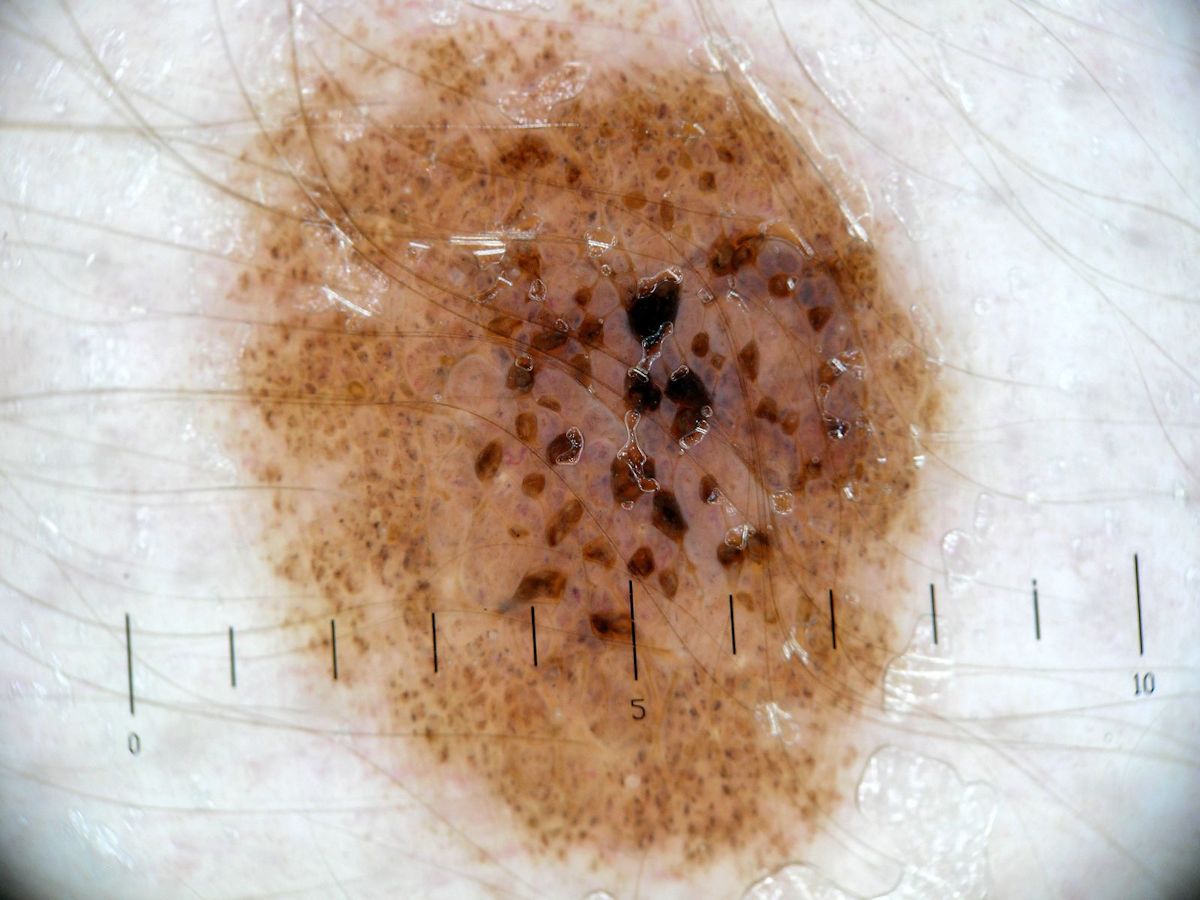

naevus naevocellularis (dermalis) papillomatosus

is een licht tot donkerbruine melanocytaire naevus, meestal wat groter dan gewone

naevi (1-2 cm), meestal op de romp maar soms ook in het gezicht, met sterke

papillomateuze uitgroei. Soms wratachtig oppervlak door hyperkeratose. Vaak

zijn er ook hoorncysten waardoor de laesie kan lijken op een verrucae seborroica.

dermatoscopie |